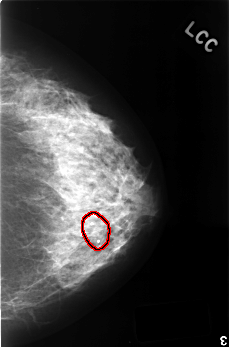

C_0407_1.LEFT_CC

FILE: C_0407_1.LEFT_CC.OVERLAY

TOTAL_ABNORMALITIES 1

ABNORMALITY 1

LESION_TYPE CALCIFICATION TYPE DYSTROPHIC DISTRIBUTION SEGMENTAL

ASSESSMENT 2

SUBTLETY 5

PATHOLOGY BENIGN_WITHOUT_CALLBACK

TOTAL_OUTLINES 1

BOUNDARY